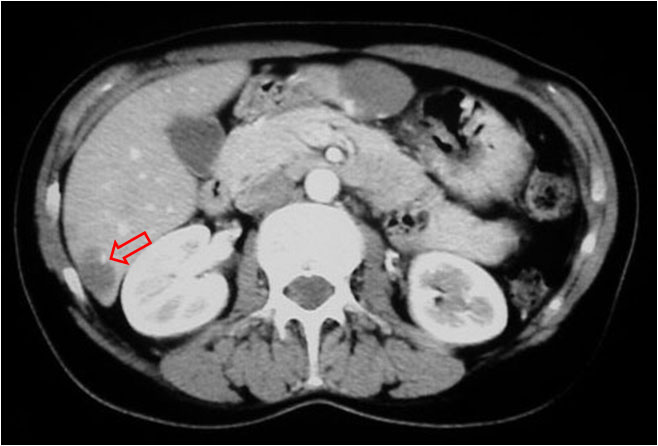

SIGNO DEL PUNTO BRILLANTE

Signo de hemangioma de comportamiento atípico. En el estudio de TC helicoidal de doble fase (fase arterial hepática y fase venosa portal), la mayoría de hemangiomas presentan un realce más precoz en la periferia y más tardío en el centro, pero hay hemangiomas atípicos que muestran una hipodensidad mantenida en las dos fases. La mayor parte de estos últimos muestran un punto brillante o más en al menos una de las dos fases.

El signo representa el relleno de contraste de un espacio vascular (flecha).

La referencia bibliográfica de este signo es: Hyun-Jung Jang y cols. Atypical small hemangiomas of the liver: «bright dot» sign at two-phase spiral CT. Radiology 1998; 208:543-548.